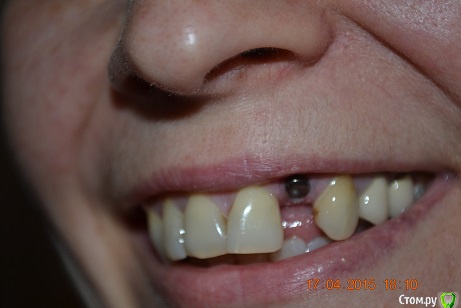

nat-man Опубликовано 17 апреля, 2015 Автор Поделиться Опубликовано 17 апреля, 2015 вот как-то так Ссылка на комментарий

red_butler Опубликовано 17 апреля, 2015 Поделиться Опубликовано 17 апреля, 2015 требуется пластика десны Ссылка на комментарий